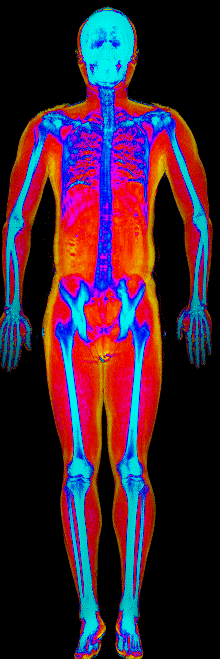

What Fat Loss Looks Like on a DEXA Scan

Red = muscle, gold = fat, blue = bone.

Lost 26.0 lb of fat · 187 → 150 lb · Age 44

Lost 25.4 lb of fat, gained 3.7 lb lean · 201 → 180 lb · Age 33

Lost 24.9 lb of fat, gained 12.0 lb lean · 183 → 170 lb · Age 37